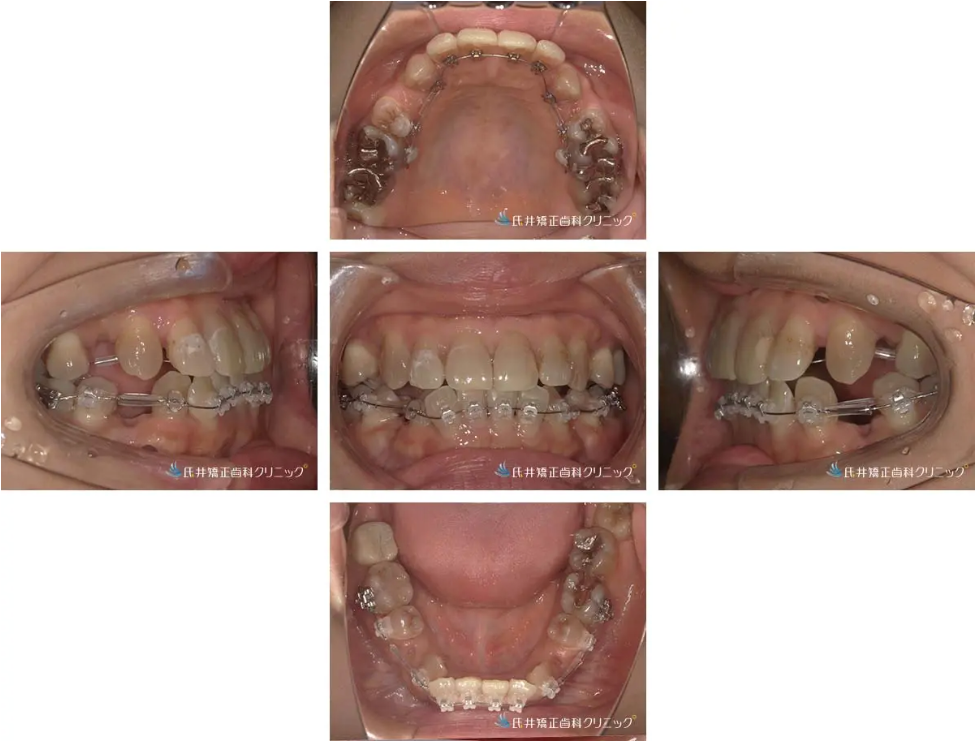

治療経過①:抜歯を行い、歯を動かす準備が整いました「1ヶ月後」

治療開始から約1か月後、スペースを確保するために抜歯を行いました。

抜歯後にはワイヤーを調整し、歯をゆっくりと正しい位置へ導く準備段階に入っています。

治療経過②:4か月後の変化

治療開始から4か月が経過しました。

この時点で、上下の歯の重なりが少しずつ整い、正面から見ても自然なアーチが形成されてきました。

裏側の装置は見えない位置にありますが、確実に歯が動いており、患者さんも「見えないのにちゃんと動いているのが嬉しい」と実感されています。